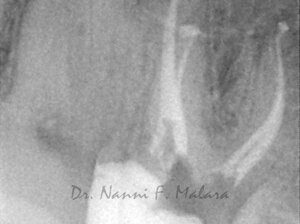

Molare affetto da lesione periapicale a carico di entrambe le radici (Alla radiografia si presentano come aree scure intorno alle radici)

Terapia endodontica con sigillo tridimensionale dei canali radicolari

Controllo della guarigione a 7 mesi dalla terapia endodontica (Alla radiografia si nota come le lesioni ossee siano guarite, e la densità della trabecolatura ossea sia tornata alla normalità)